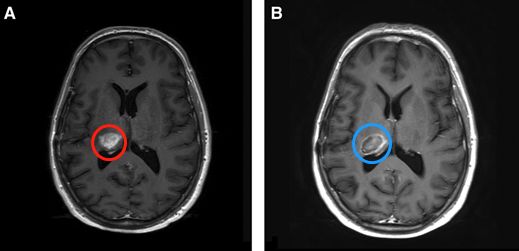

在60°C時會發(fā)生凝結(jié)性壞死引起的瞬時細(xì)胞死亡。在43°C至60°C之間的溫度下,時間和溫度的組合主要通過凋亡導(dǎo)致細(xì)胞死亡。這兩個系統(tǒng)至少部分地依賴于要消融的病變的對比光學(xué)特性以及要保留的周圍更正常的腦組織。結(jié)果,所產(chǎn)生的病變可以相對符合目標(biāo)病變的邊界。此外,這兩個LITT系統(tǒng)還利用了自然散熱器(例如相鄰的溝和水箱以及周圍的血管系統(tǒng))的優(yōu)勢,以防止熱量傳播到潛在的雄辯結(jié)構(gòu)(圖1和2)。LITT可以消融鉆孔開顱手術(shù)和傳統(tǒng)的開放式手術(shù)都難以進(jìn)入得深部病變(圖3)。由于溫度梯度迅速下降到消融區(qū)域之外,因此周圍正常的腦組織無需進(jìn)行熱消融。

圖2:45歲男性,間變性少突膠質(zhì)細(xì)胞瘤術(shù)后復(fù)發(fā),LITT激光消融前(A)和消融后(B)。消融區(qū)向沿著中央前溝、避免損傷初級運(yùn)動皮層。